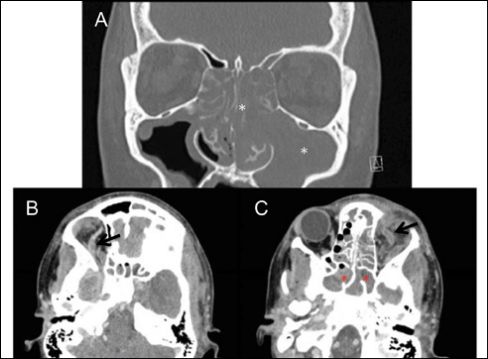

行头部和眼眶CT(图2)和MRI/MRV检查(图3),影像学显示双侧眼静脉充盈缺损和双侧合并低强化区,扩散受限,与海绵窦血栓形成表现相一致。同时,请耳鼻喉科、神经外科及传染科会诊。行鼻内镜手术及拔牙,术中行血液及鼻窦培养,术后立即全身抗凝。左眼给予布鲁莫尼丁,每日3次。

图2. 有无对照头部及眼眶CT扫描均可见广泛的窦性混浊(a,白色星号),右眼静脉扩张(b,黑色箭头),左眼静脉扩张(c,黑色箭头),蝶窦混浊(c,红色星号)